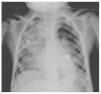

In another x-ray, diffuse radiopacity of right lung predominance was identified, which showed an air bronchogram in its interior, extending from the apical lobe to the base of the same lung, with probable zones in the parahilar region related with a pneumonic process. The cardiophrenic and costodiaphragmatic angles are free. The cannula was identified inside the trachea in good position. The remainder of the structures did not reveal any apparent changes (Fig. 2). In a follow-up study, a thoracoabdominopelvic projection was taken in which persistence of areas of consolidation previously mentioned are noted as well as air fluid levels (Fig. 3).

Figure 2 Chest study where aliveolar-type nfiltrate is identified in both pulmonary fields with right predominance.

Figure 3 Thoracoabdominal projection with pneumonic foci in the right lung and air levels in the intestine with distal air.